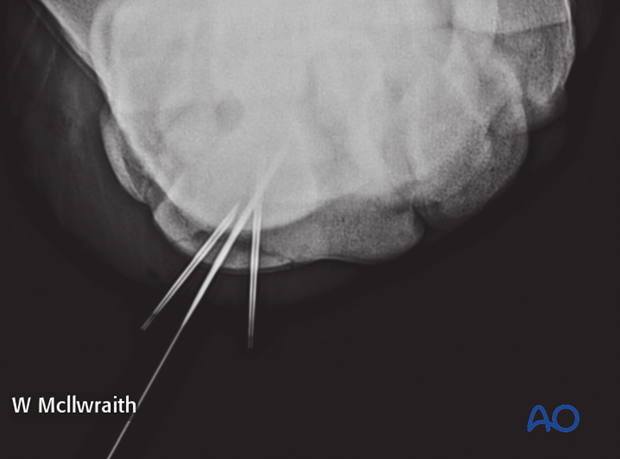

Intraoperative radiographs are take to confirm screw length and correct positioning.

Intraoperative radiographs are taken to confirm screw length and correct positioning.